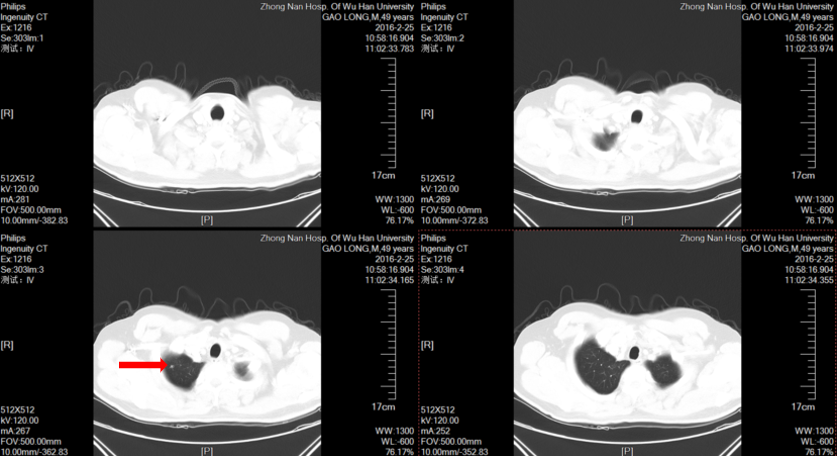

2016.2.25:

第5次PD

会阴部双下肢背侧疼痛加重,

MRI左侧闭孔内肌及梨状肌M;左髂骨M

CT双肺多发结节。

影像学检查:

2016.2.25:左侧闭孔内肌及梨状肌信号异常;左髂骨异常信号。

2016.2.25胸部CT:双肺多发结节。